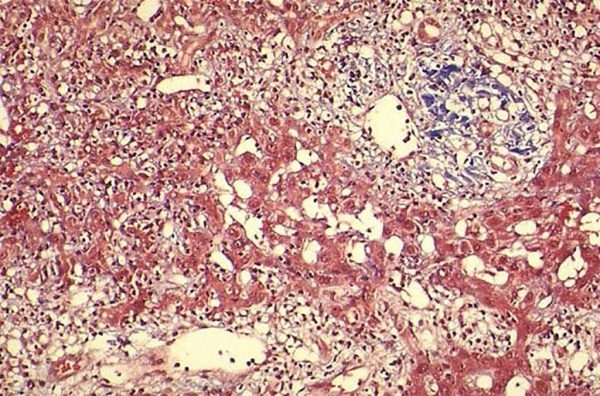

Цирроз печени – возникает в результате продолжительного повреждения печени. Острое желудочно-кишечное кровотечение - серьезное осложнение у пациентов с циррозом печени. В Китае основной причиной цирроза является вирус гепатита B (HBV).